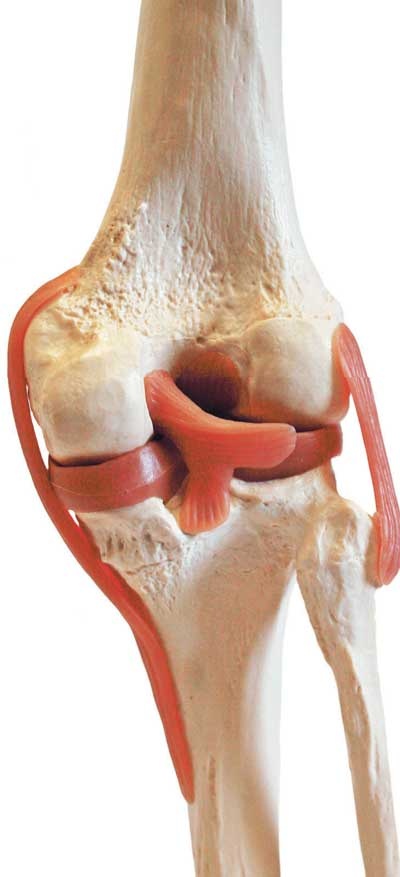

![]() Отделы позвоночника Движение позвоночника – результат работы многочисленных комбинированных суставов между позвонками. Он движется за счет действия скелетных мышц. Позвоночник способен наклоняться вперед, прогибаться (сгибание и разгибание), наклоняться вбок (отведение и приведение), а также скручиваться. Наиболее подвижны шейный и поясничный отделы. Химический состав костей взрослого человека следующий: 50 % воды, 15 % жира, 12 % органических веществ (белок, представляющий собой разновидность коллагена), 22 % неорганических веществ, а именно солей кальция в форме гидроксиапатита, и около 30 % органических веществ. Основные органические вещества кости – белки коллаген и оссеин. Сочетание волокон органического коллагена с солями кальция обеспечивает основные функции костей – прочность и упругость. Прочность – это способность противостоять внешним механическим воздействиям, упругость – возвращать первоначальную форму после окончания действия внешней силы. Минеральные вещества придают костям твердость и хрупкость, органические – гибкость и упругость. Благодаря сочетанию органических и неорганических веществ кости имеют большую прочность, что позволяет им выносить немалые нагрузки. ![]() Структура кости Соотношение органических и неорганических веществ с возрастом изменяется. В костях детей немного больше органических веществ, поэтому их кости более упругие, гибкие и реже ломаются. С возрастом в костях увеличивается доля неорганических веществ, из-за чего у пожилых людей кости менее эластичные и более хрупкие и могут ломаться даже при небольших травмах. Соединения костей связывают кости скелета в одно целое, обеспечивая им ту или иную степень подвижности. Различают три вида соединений: • непрерывные соединения, в которых полость между соединяющимися костями отсутствует, существует лишь прослойка соединительной ткани или хряща – неподвижные соединения; • переходная форма от непрерывных соединений к прерывным – симфизы, или полусуставы; имеют небольшую щель в хрящевой или соединительнотканной прослойке между сочленяющимися костями – эти образования обладают большой прочностью и очень ограниченной подвижностью; • прерывные (синовиальные) соединения или суставы; характеризуются наличием между костями полости и синовиальной оболочки, выстилающей изнутри суставную капсулу, – это подвижные соединения, а степень подвижности зависит от особенностей строения конкретного сустава. Сустав – самая распространенная и сложная форма соединения костей. Обязательными элементами любого сустава, независимо от места расположения и степени подвижности, являются суставные поверхности, суставная сумка и суставная полость. ![]() Соединение костей в коленном суставе (вверху – рентген, внизу – модель) ![]() Суставные поверхности костей, образующие сустав, плотно прилегают друг к другу. Они покрыты особым гиалиновым хрящом, чья гладкая поверхность и эластичность облегчают движение в суставе, смягчают испытываемые им толчки и сотрясения. Суставные поверхности костей окружает суставная капсула – оболочка из соединительной ткани. Обычно она крепится к костям в месте перехода суставной поверхности в надкостницу и прочно с ней срастается. Снаружи капсула укреплена связками, которые располагаются в местах наибольшей нагрузки. Суставные поверхности и капсула ограничивают собой небольшое герметично закрытое пространство – полость сустава, заполненную малым количеством вязкой синовиальной жидкости, роль которой заключается в уменьшении трения в суставах при движении. Благодаря отрицательному давлению в суставной полости поверхности костей тесно прилегают друг к другу. ![]() Суставная капсула ![]() Шаровидный сустав По форме суставных поверхностей различают плоские, цилиндрические, эллиптические и шаровидные суставы. Наименее подвижны плоские суставы, наиболее – шаровидные. Так как мы существуем в трехмерном пространстве, то в биомеханике суставов соответственно выделяют три оси вращения: фронтальную (правая – левая стороны, или наружная – внутренняя поверхности), сагиттальную (задняя – передняя поверхности) и продольную (вдоль сочленяющихся костей). В зависимости от формы суставных поверхностей в суставах может быть движение вокруг любой одной, двух или трех указанных осей (одно-, двух- и многоосные суставы). Вокруг указанных осей выполняются соответствующие виды движений. Вокруг фронтальной оси происходят сгибание и разгибание. При сгибании угол между сочленяющимися костями уменьшается (например, в локтевом суставе – угол между плечом и предплечьем). Во время разгибания движение идет в обратном направлении и происходит выпрямление (конечности или туловища). Вокруг сагиттальной оси осуществляются приведение и отведение. В случае отведения одна из сочленяющихся костей удаляется от срединной плоскости, при приведении – приближается к ней (например, отведение руки в сторону от туловища и снова приближение к нему). ![]() Наши двигательные возможности определяются прежде всего строением суставов Вокруг продольной оси кость вращается в разные стороны. Круговое движение – это последовательное перемещение вокруг всех осей, при котором свободный конец движущейся кости или конечности (например, кисти руки) описывает окружность. Размах (объем) движений в суставах зависит от многих факторов: • от разности угловых величин (выражаются в угловых градусах) сочленяющихся поверхностей (чем больше эта разность, тем больше размах движений); |